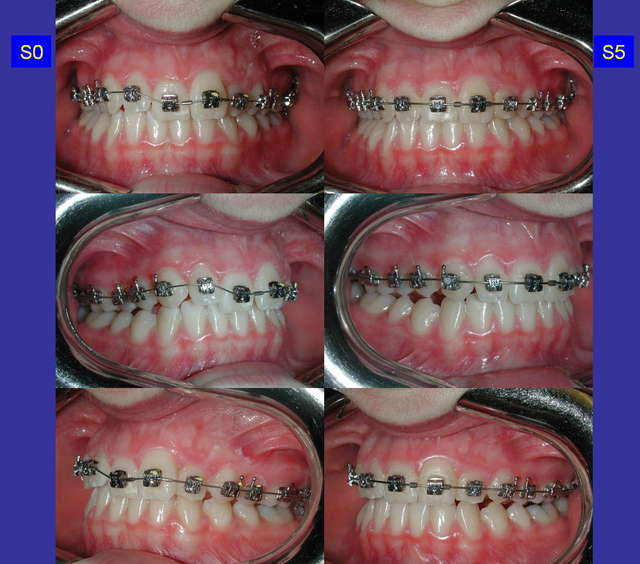

17/03/2006 à 22h47

suite...

arc .018 Niti maxillaire

empreinte mandibulaire pour collage indirect 7 à 7

Capturer 3 tglluv - Eugenol

Capturer 3 ypqivb - Eugenol